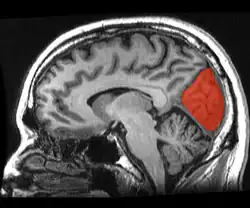

Cuneus

![]() Sagittal MRI slice with the cuneus and lingual gyrus shown in red. | |

The cuneus (from Latin 'wedge'; pl.: cunei) is a smaller lobe in the occipital lobe of the brain. The cuneus is bounded anteriorly by the parieto-occipital sulcus and inferiorly by the calcarine sulcus.

The cuneus (Brodmann area 17) receives visual information from the same-sided superior quadrantic retina (corresponding to contralateral inferior visual field). It is most known for its involvement in basic visual processing. Pyramidal cells in the visual cortex (or striate cortex) of the cuneus, project to extrastriate cortices (BA 18,19). The mid-level visual processing that occurs in the extrastriate projection fields of the cuneus are modulated by extraretinal effects, like attention, working memory, and reward expectation.